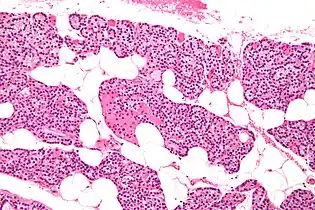

Microanatomy

The parathyroid glands are named for their proximity to the thyroid—and serve a completely different role than the thyroid gland. The parathyroid glands are quite easily recognizable from the thyroid as they have densely packed cells, in contrast with the follicular structure of the thyroid.[6] Two unique types of cells are present in the parathyroid gland:

• Chief cells, which synthesize and release parathyroid hormone. These cells are small, and appear dark when loaded with parathyroid hormone, and clear when the hormone has been secreted, or in their resting state.[7]

• Oxyphil cells, which are lighter in appearance and increase in number with age,[7] have an unknown function.[8]